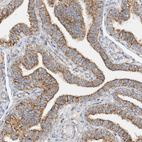

Immunohistochemical staining of human kidney shows strong granular cytoplasmic positivity in cells in tubules.